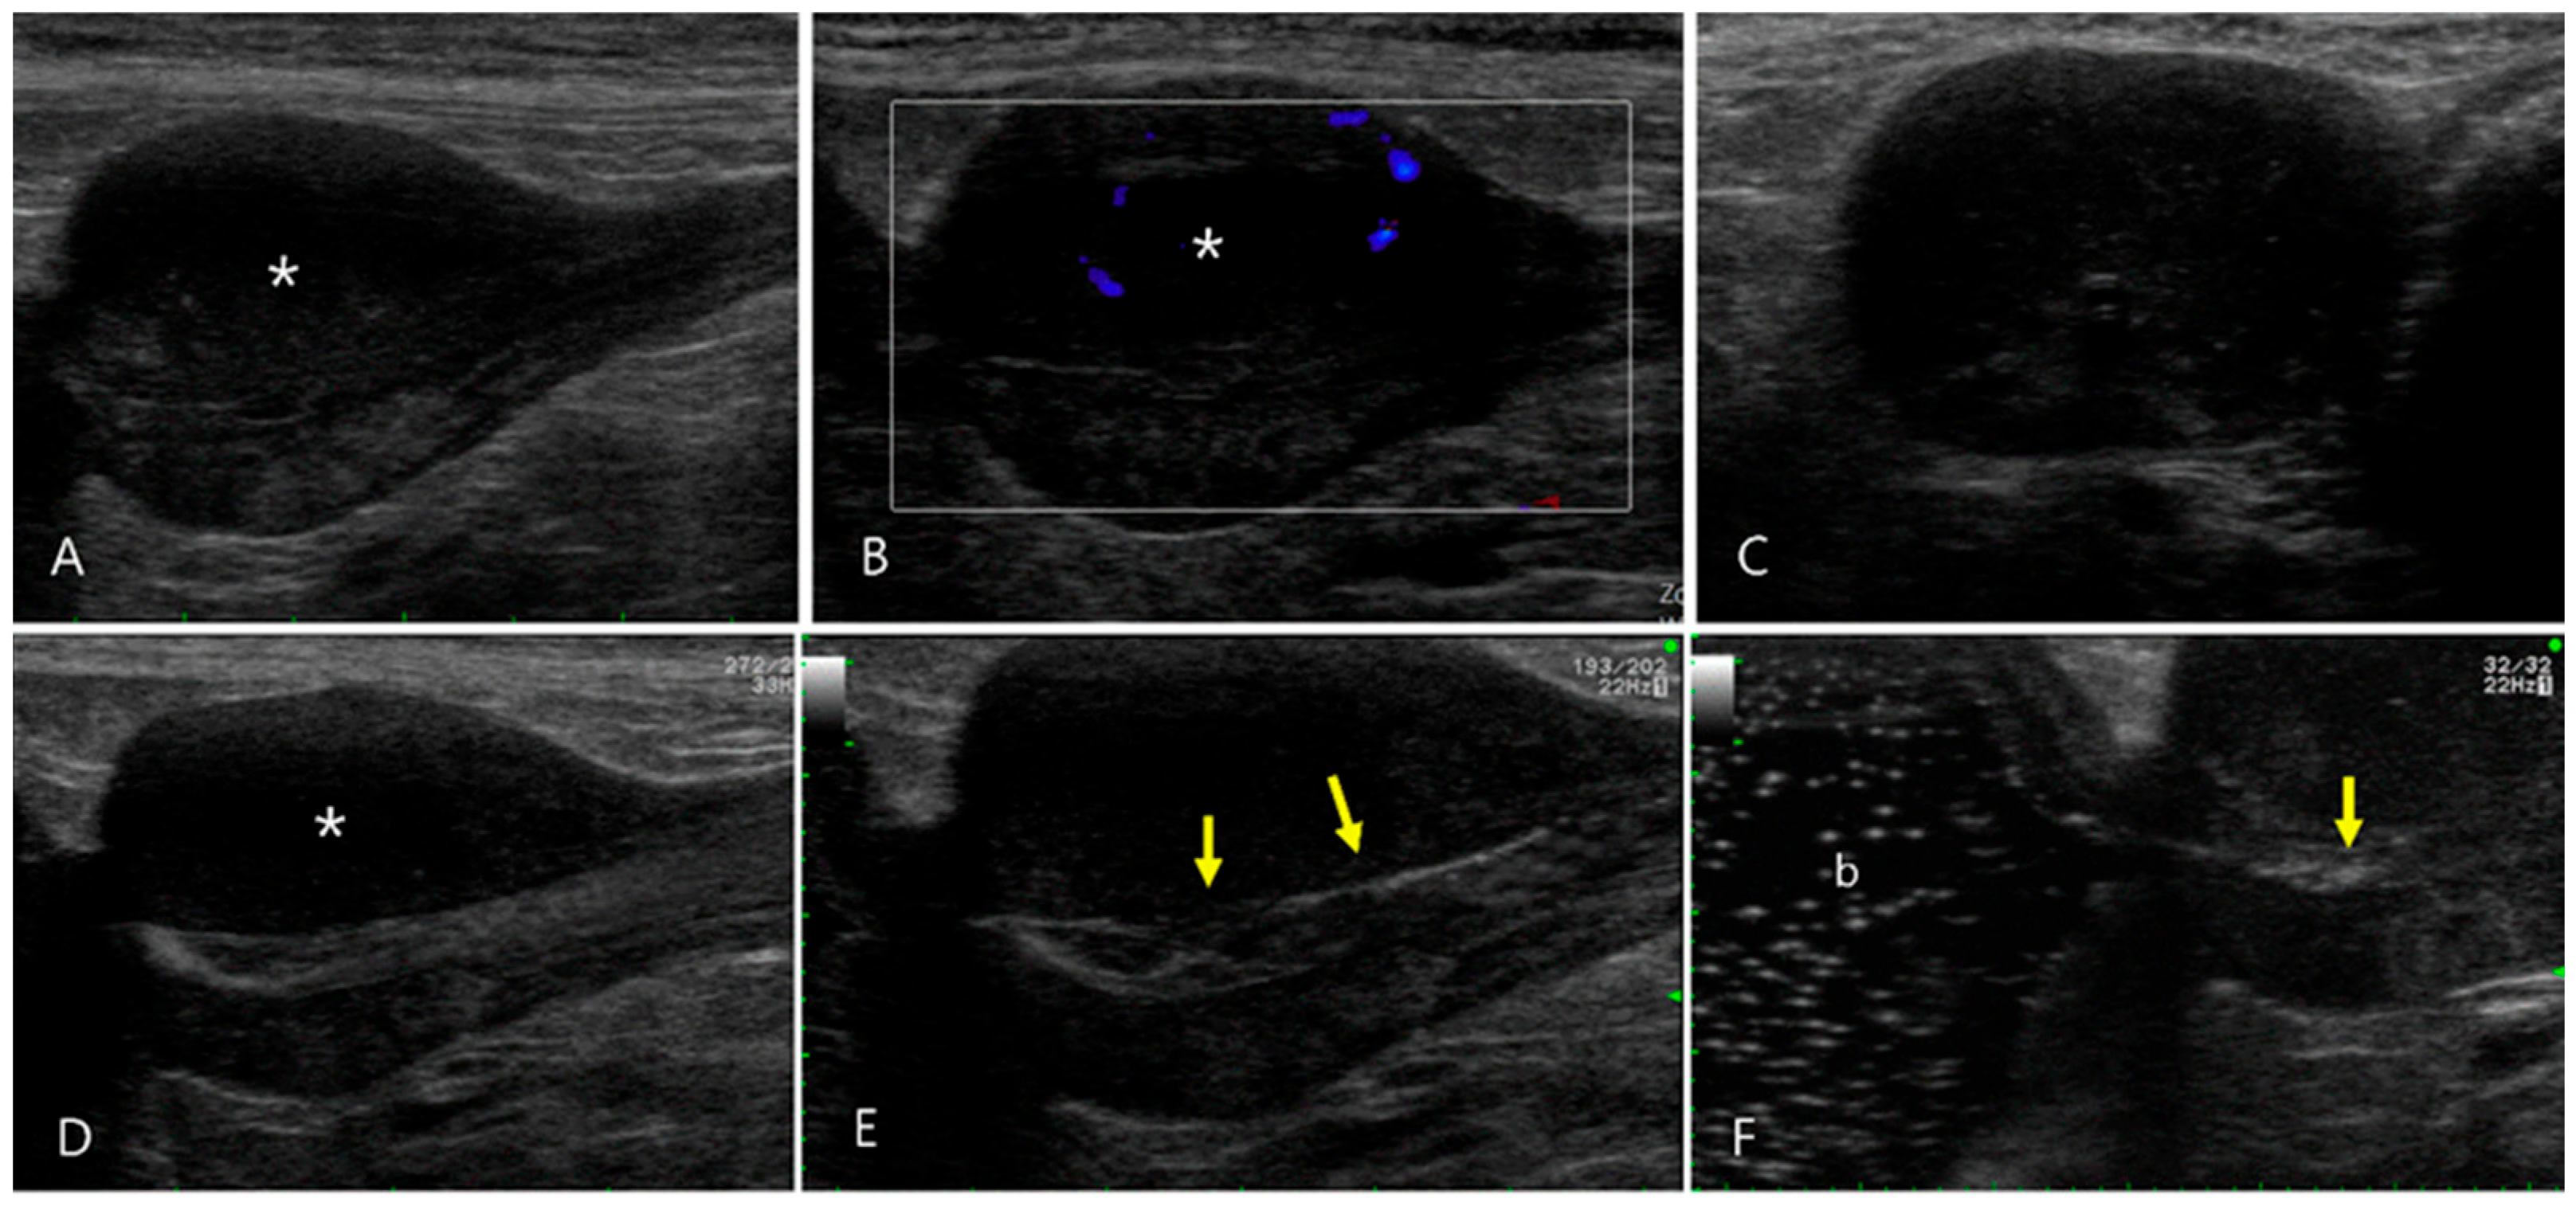

2.4. Case 4

2.5. Case 5

2.6. Case 6